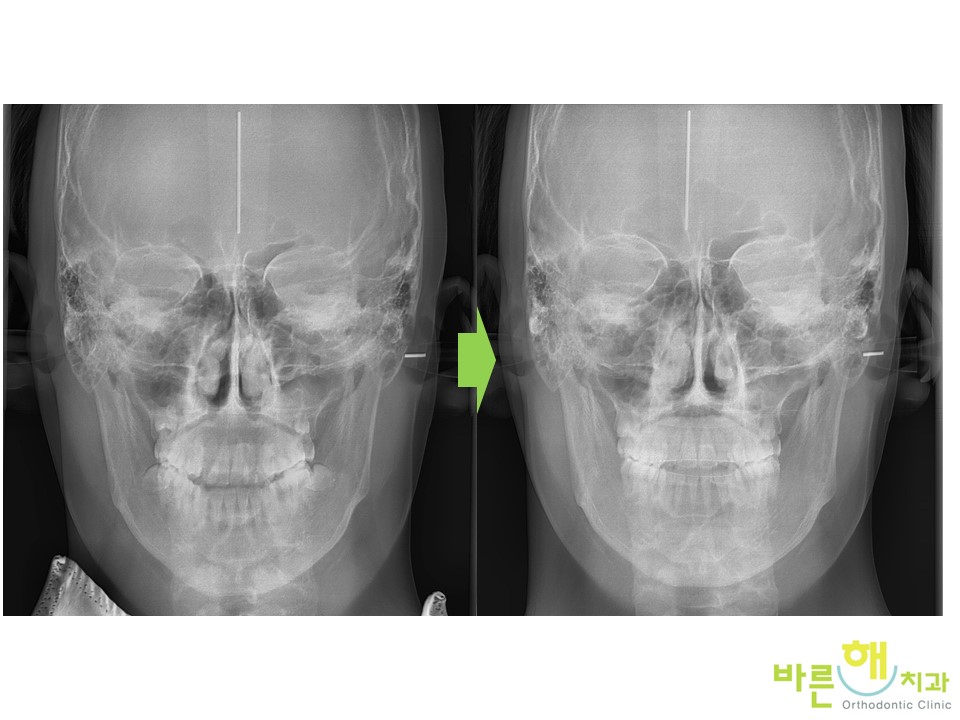

ºñ¼ö¼ú ÁÖ°ÆÅÎ ±³Á¤ Ä¡·á ÀüÈÄÀÔ´Ï´Ù.

¾È¸éºñ´ëĪÀÌ ¸¹ÀÌ °³¼±µÈ °ÍÀ» º¼ ¼ö ÀÖ½À´Ï´Ù.